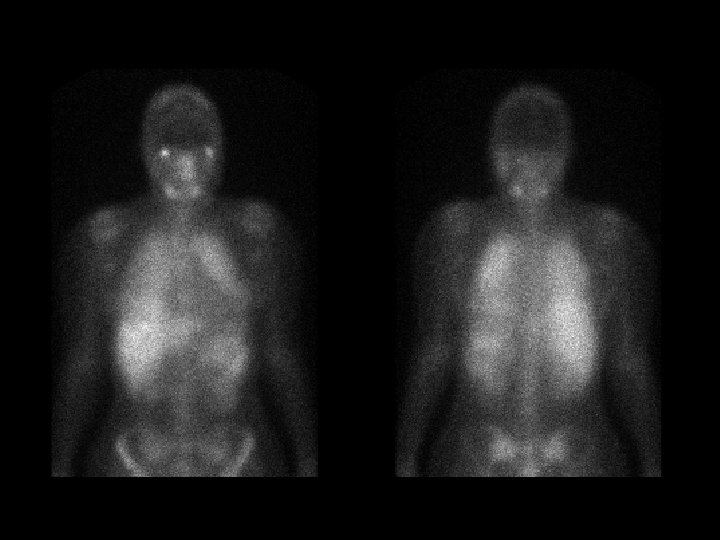

Tuberculosis & AIDS • • • Ga-67 citrate 5 -10 m. Ci, i. v. images obtained at 72 hrs diffuse lymph node activity in the chest & abd intense splenic activity gallium binds transferrin (liver) and lactoferrin (salivary and lacrimal glands, nasopharynx, spleen, and bone marrow) ddx: – lymphoma – sarcoid – infection (abscesses)